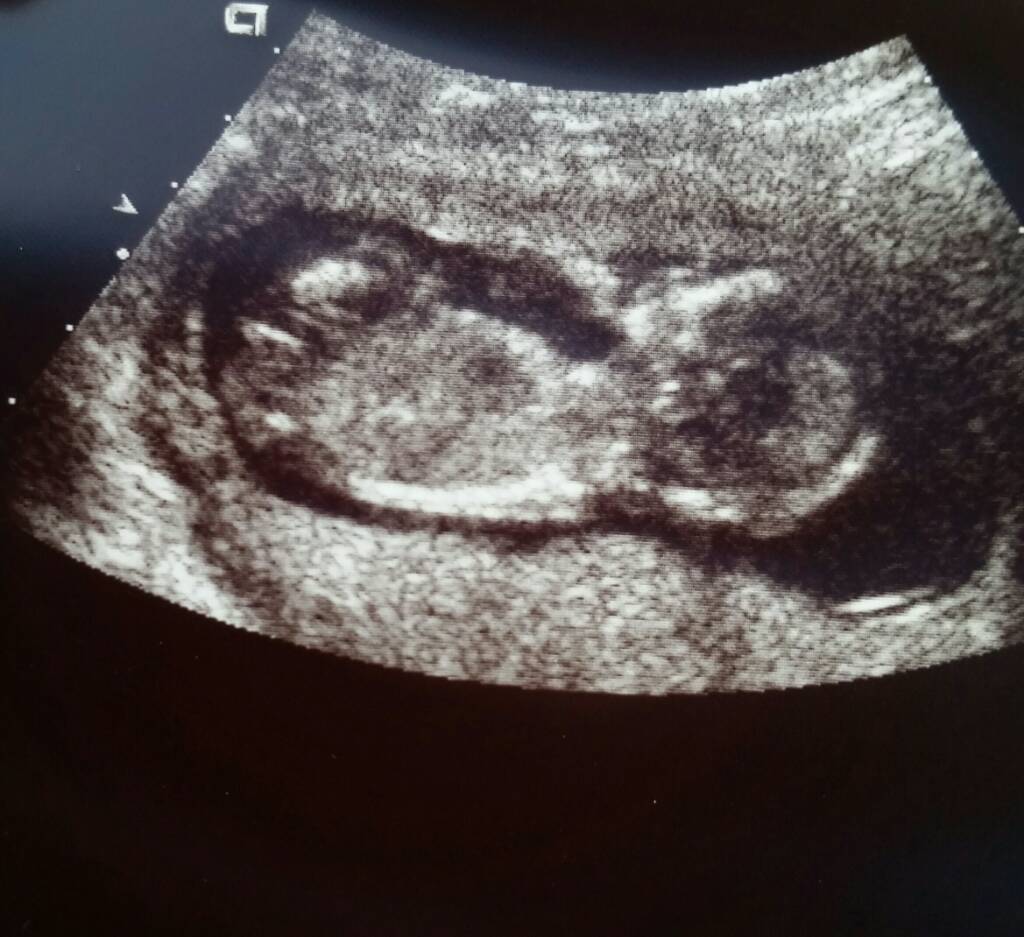

Does this look like a boy nub or girl nub to you? I was told girl once, but I wanted to get more opinions. Thank you.![]()

Nub theory at 13 weeks 4 days

girl

I would guess girl